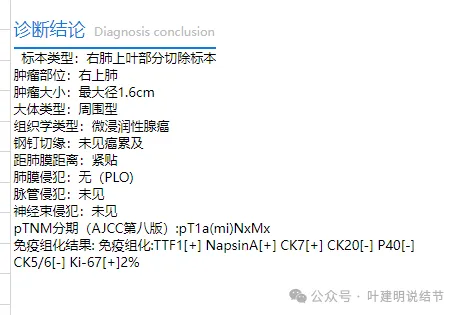

最后结果:

与患者及家属充分沟通后,考虑选择单孔胸腔镜下右上叶部分切除。

病灶切面灰白,没有包膜,与周围正常组织界限不清。

术中快速切片示腺癌,呈贴壁状生长。

常规病理示:微浸润性腺癌。